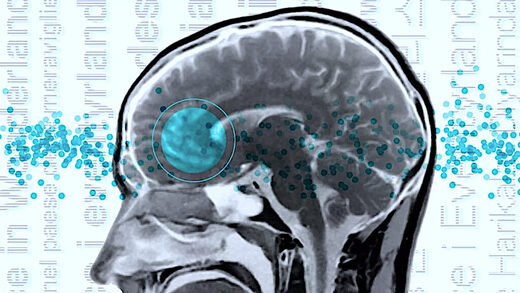

В исследовании, опубликованном в журнале Nature Neuroscience, приняли участие два носителя каждого языка, которые проходили сканирование мозга во время выполнения различных когнитивных задач. В частности, команда сканировала мозг участников с помощью метода функциональной магнитно-резонансной томографии (фМРТ), который отслеживает поток насыщенной кислородом крови в мозге. Активные клетки мозга требуют больше энергии и кислорода, поэтому МРТ позволяет косвенно измерить активность клеток мозга.

У носителей английского языка области мозга, активизирующиеся при обработке языка, находятся в основном в левом полушарии мозга, главным образом в лобной доле, расположенной за лбом, и в височной доле, расположенной за ухом. Построив "карты" активности мозга всех испытуемых, исследователи обнаружили, что эти же области мозга активизируются независимо от услышанного языка.